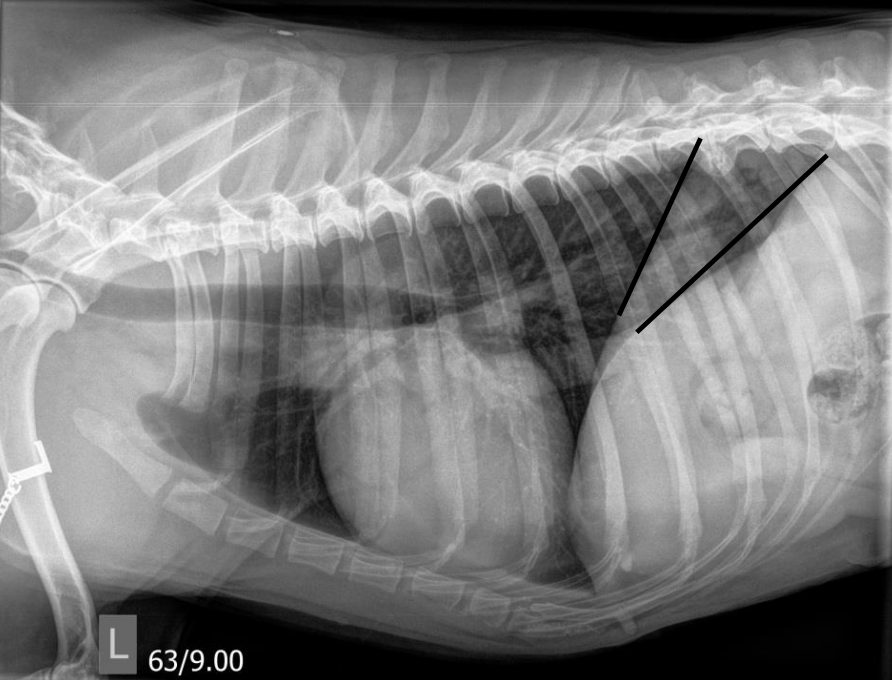

what is demonstrated by the lines

crura of diaphragm V shaped left lateral

heart shorter, rounded and less contact with sternum